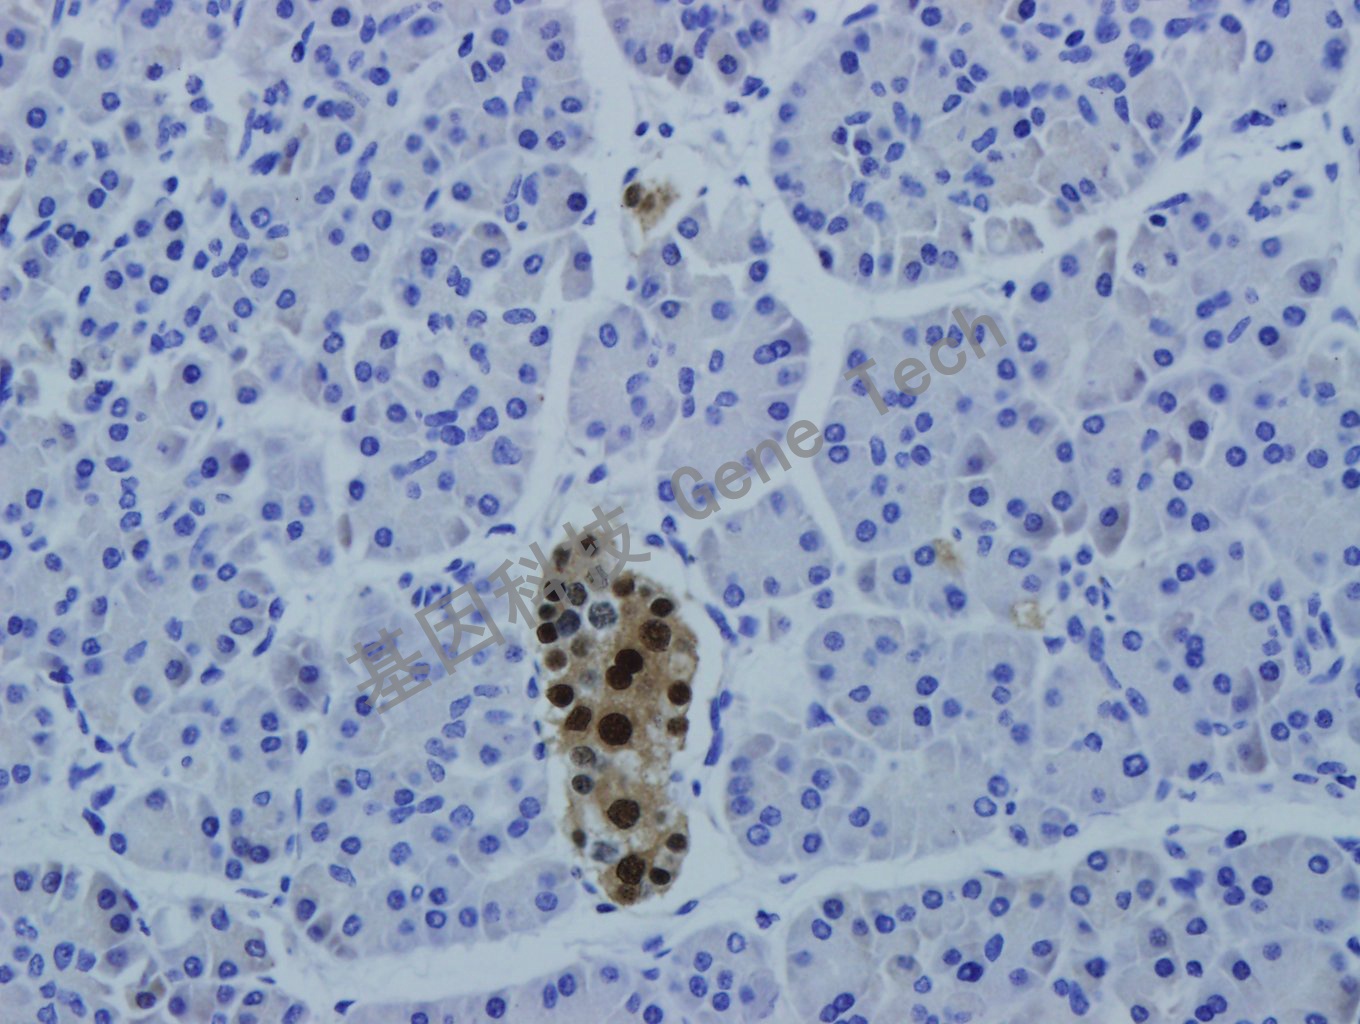

胰腺癌石蜡切片,用 PAX-6(GT2278)染色,细胞核阳性,DAB显色。(10×)

胰腺癌石蜡切片,用 PAX-6(GT2278)染色,细胞核阳性,DAB显色。(40×)